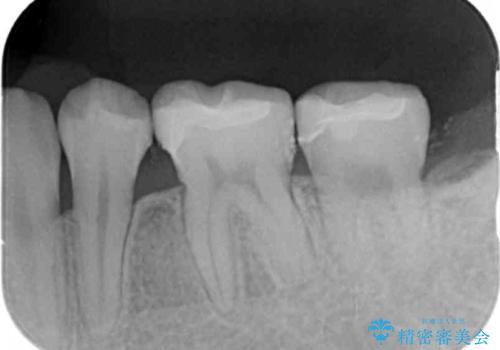

- 矯正治療終了後、前々から気になっていた笑った時に見える銀歯を白くしたいと希望され来院されました。

銀歯を拡大鏡下で丁寧に除去したのち、小さな虫歯も除去し精密で適合の良いセラミックインレーによる再修復を行います。

笑った時に見える銀歯は口元の印象を大きく変えます。矯正治療後のきれいな歯並びに加えて銀歯がなくなったことでより口元の明るい印象になりました。